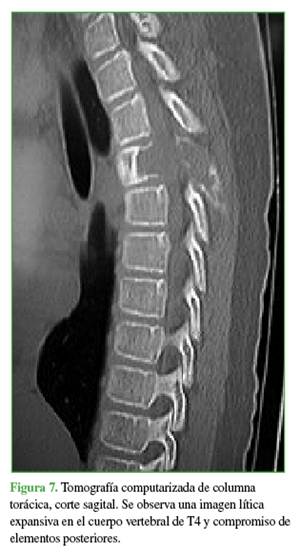

La zona afectada era 3-6, niveles III y IV de la clasificación de Weinstein-Boriani-Biagini.11 En los estudios complementarios, se observaron múltiples quistes tabicados con niveles líquido-líquido, por lo que se descartó un quiste óseo simple, de características expansivas y compresivas, ante este patrón se descartó la posibilidad de un hemangioma vertebral (Figuras 7 y 8). Este caso también se interpretó como una lesión secundaria a un QOA grado 3 de Enneking.13

El plan terapéutico consistió en descomprimir de manera urgente y estabilizar la columna vertebral, en un primer tiempo quirúrgico, y disminuir el riesgo de sangrado mediante una embolización selectiva, con un segundo tiempo de estabilización y artrodesis.

Se realizó el primer tiempo quirúrgico dentro de las 24 horas. Este consistió en una descompresión del canal medular mediante una resección del arco posterior de T4, y una corpectomía por costo-transversectomía mediante una técnica de vaciado corporal con preservación del borde cortical (eggshell).14 Se estabilizó la columna con una fijación pedicular de T2-T6.